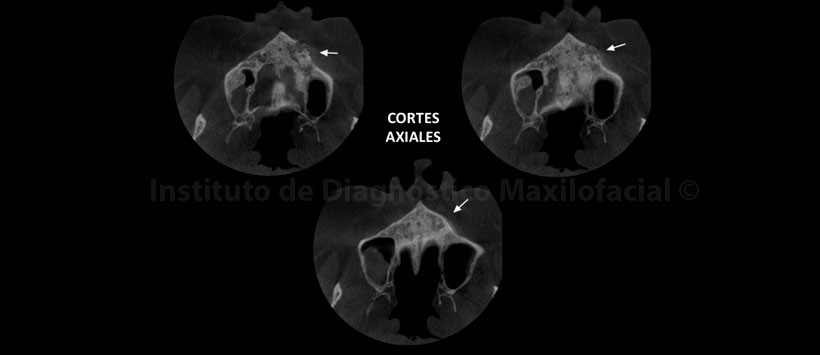

A la evaluación de la tomografía volumétrica (CBCT) en los cortes axiales (Figura 2, 3), coronales (Figura 4,5), transaxiales (Figura 6,7) y tangenciales (Figura 8), se aprecia proceso osteolítico de límites mal definidos, bordes difusos, localizado a nivel del maxilar superior del lado izquierdo, que se extiende en sentido mesio-distal desde la pieza 2.2 hacia los lechos alveolares de las piezas 2.3 y 2.4 y en sentido cefálico-caudal de la címa de reborde alveolar hasta el piso del seno maxilar a nivel de la zona de pieza 2.5. Se aprecia, presencia de secuestros óseos y reacción periostal en la tabla ósea vestibular y en zona del piso del seno maxilar.